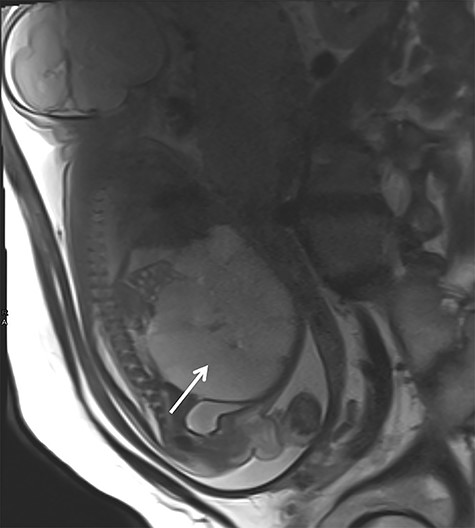

After birth, the male baby presented in good general condition with stable vital signs. The abdomen was distended but not painful on palpation. Postnatal ultrasound confirmed the lesion. To assess the exact extend, MRI was performed showing a macrocystic LM occupying the entire abdomen (Fig. 2) without ascites. However, the exact origin of the lesion and the amount of extension into the mesenteric root could not be described.

Postnatal abdominal MRI. The bowel loops are displaced into the upper part of the abdomen. The exact origin of the lymphatic malformation could not be described.